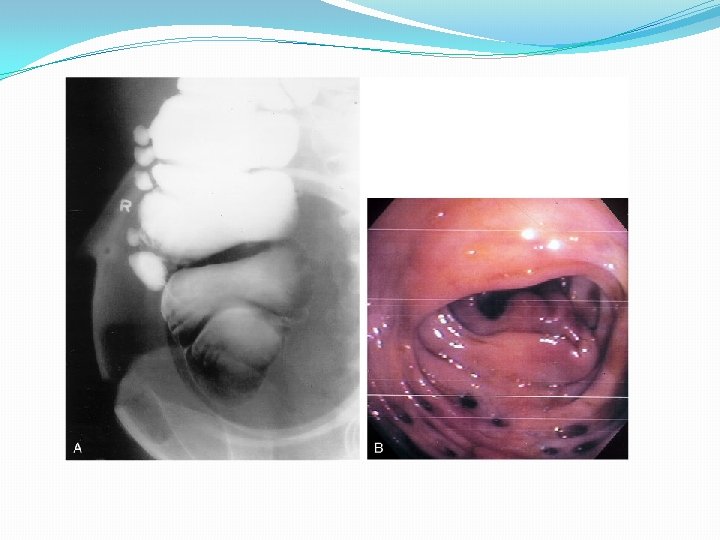

• Rx • Colonoscopia

Diagnóstico • Rx Simple • Tórax • Abdomen • Enema baritado y colonoscopia: contraindicados en fase aguda • Enema hidrosoluble • TAC helicoidal • ECO

• Rx Simple • Tórax: • Abdomen • Enema baritado y colonoscopia: contraindicados en fase aguda • Enema hidrosoluble • TAC helicoidal • ECO

• Rx Simple • Tórax: • Abdomen • Enema baritado y colonoscopia: contraindicados en fase aguda • Enema hidrosoluble • TAC helicoidal • Engrosamiento pared Intestinal • Grasa mesentérica en franjas • Abscesos • ECO • Engrosamiento pared colónica • Masas

• Rx Simple • Tórax: Perforación • Abdomen • Dilatación de ID y de IG • Obstrucción intestinal • Opacidades de partes blandas: abscesos • Enema baritado y colonoscopia: contraindicados en fase aguda • Enema hidrosoluble • TAC helicoidal • Engrosamiento pared Intestinal • Grasa mesentérica en franjas • Abscesos • ECO • Engrosamiento pared colónica • Masas